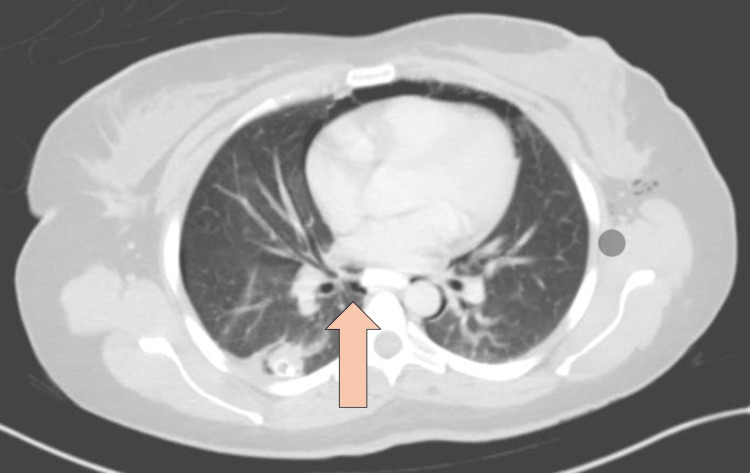

CT abdomen with IV and oral contrast post-ERCP showed pneumobilia with evidence of stent in the biliary system seen in a satisfactory position, significant pneumoretroperitoneam, small amount of retroperitoneal leaked contrast inferior to the second part of the duodenum, bulky and edematous pancreatic head, and uncinate process suggestive of acute pancreatitis, no intra-abdominal collection, and minimal amount of free fluids. There was extensive soft tissue emphysema along the anterior neck, lateral chest, and abdominal wall, severe pneumomediastinum, and minimal bilateral pneumothoraxes, with a chest tube seen on the right side in a satisfactory position, and a tiny area of contrast leakage was seen in the right posterior-lateral of the mid esophagus at T6 (Figures 2–4). The impression was double perforation at the second part of the duodenum and esophagus.